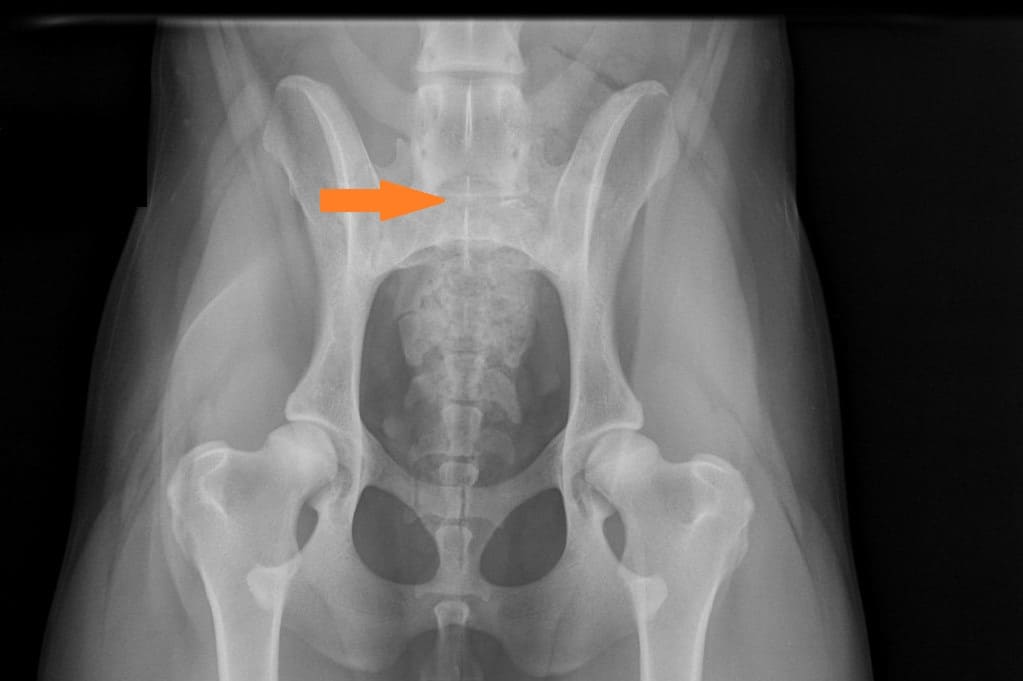

LTV3; asymmetrical; on the right in the VD photo the left side of S1 is shaped like a sacral vertebra and on the right side S1 is shaped like a lumbar vertebra including the spinous process.

The asymmetrical form, LTV3, seems to be a bit more tricky than the other forms. In some cases asymmetrical form comes with rotated pelvis, which might lead to unilateral development in hips. This is actually very logical; when the pelvis is not straight and in balance there will be uneven bear of weight between hips. In long term this uneven state might cause the worse hip wear sooner than the better hip and lameness and osteoarthritis may occur.

In the Finnish Kennel Club’s database 38,9% of Rhodesian Ridgebacks with LTV3 have one hip scored 1-2 degrees lower than the other one, ie. A/C (Oct 2020). The score doesn’t tell if the dog’s pelvis is straight or rotated.

“Asymmetrical LTV favours pelvic rotation over its long axis, resulting in inadequate femoral head coverage by the acetabulum on one side. Inadequate coverage of the femoral head favours subluxation, malformation of the hip joint, and secondary osteoarthritis. Asymmetrical hip conformation may therefore be the sequela of a LTV and mask or aggravate genetically induced canine hip dysplasia.”

(Flückiger M., Frank Steffen F. et al 2017)